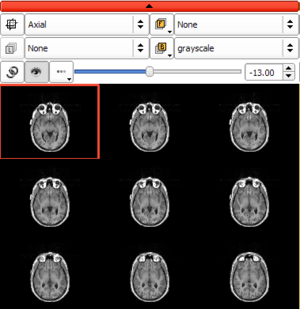

| qMRMLSliceWidget |

|

a 2D vtk render window with a controller |